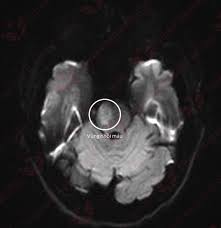

Đột quỵ não – một trong những căn bệnh gây tử vong hàng đầu hiện nay và để lại di chứng hết sức nặng nề. Việc phổ biến những dấu hiệu nhận biết, nguy cơ cảnh báo và “thời gian vàng” để cấp cứu kịp thời tới người dân là chìa khóa khống chế hậu quả, giảm tỷ lệ người mặc bệnh.

Cerebral stroke is one of the leading causes of death today and often leaves severe long-term complications. Raising public awareness about the warning signs, risk factors, and the “golden time” for emergency treatment is the key to minimizing consequences and reducing the number of cases.